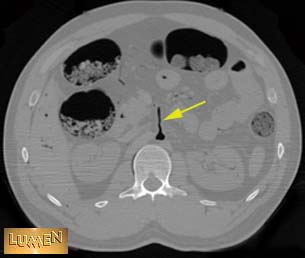

Question: Identify.

Answer

Superior mesenteric v.